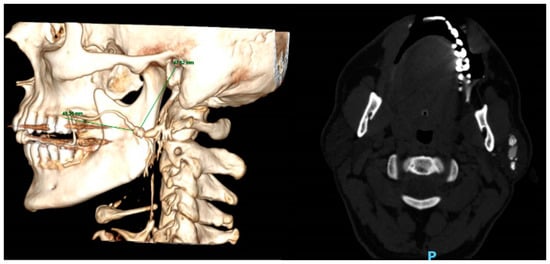

- Sialolith characteristics (according to CT)

- Size (Figure 1): length; width; height; volume (calculated by: length X width X height, we used the formula for a volume of a box as an approximation for the volume of the irregularly shaped sialoliths).

| Submandibular sialolith distance from fixed structures; (mean (mm), SD) | |

| Lingual border of the mandible | 7.9 ± 3.7 |

| Inferior border of the mandible | 31 ± 7.5 |

| Anterior border of the mandible | 39 ± 18.2 |

| Parotid sialolith distance from fixed structures; (mean (mm), SD) | |

| CEJ of the second maxillary molar | 41.8 ± 6.9 |

| External acoustic meatus | 39.6 ± 6.8 |